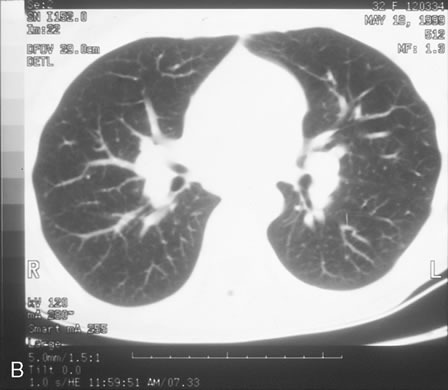

HIV infection results in depletion of T4 cells, which are central to various forms of immune responsiveness. Risk of developing AIDS is inversely related to the absolute T4 cell count. Antigen-responsive T cells become selectively depleted or functionally impaired early in the course of AIDS. There is diminished helper function for B-cell responses, depressed cytotoxic and natural killer cell responsiveness, decreased blast transformation, and decreased lymphokine production. Infected patients' B-lymphocytes spontaneously produce immunoglobulin, resulting in hypergammaglobulinemia, but are unable to produce specific antibody in response to new infections. Anergy is common. HIV also infects other cells that express the CD4 antigen, such as monocytes and macrophages, but is not cytopathic in these cells. HIV has been identified in brain capillary endothelium, oligodendrocytes, astrocytes, lymph node dendritic cells, Langerhans' cells, intestinal mucosa, myocardium, tears, corneal epithelium, aqueous, vitreous, and retina. Clinical manifestations of HIV are protean. Seropositive persons may be asymptomatic. Various acute HIV infection syndromes have been described. An acute mononucleosis-like syndrome, with fever, malaise, rash, lymphadenopathy, pharyngitis, myalgias, and arthralgias, has been noted after recent HIV exposure. Acute neurologic manifestations resembling aseptic meningitis, encephalitis, or focal lesions may be seen.25 AIDS-related complex is a somewhat ambiguous term encompassing features such as chronic fever, night sweats, weight loss, fatigue, generalized lymphadenopathy, chronic diarrhea, and laboratory abnormalities. AIDS-related complex implies an intermediate stage in the spectrum of HIV disease. CDC-defined indicator diseases include HIV encephalopathy, HIV wasting syndrome, CMV disease not involving liver, spleen or lymph nodes (26), progressive multifocal leukoencephalopathy, recurrent Salmonella septicemia, multiple or recurrent serious bacterial infections in children, extrapulmonary myobacterial infection, disseminated histoplasmosis, disseminated coccidioidomycosis, chronic isosporiasis, lymphoid interstitial pneumonia or pulmonary lymphoid hyperplasia in children, primary brain lymphoma, and various non-T–cell non-Hodgkin's lymphomas. Less specifically associated with HIV infection are manifestations of papillomavirus, molluscum contagiosum, VZV, Epstein-Barr virus, hepatitis B virus, chlamydia, gonorrhea, syphilis, campylobacter, pityrosporum, trichophyton, aspergillus, acanthamoeba, entamoeba, giardia, strongyloides, basal cell carcinoma, squamous cell carcinoma, idiopathic thrombocytopenic purpura, cerebrovascular infarction, and intracranial hemorrhage.27–30 Pneumocystis carinii pneumonia once was the most common presentation of AIDS. It is typically of insidious onset, with features including dry cough, dyspnea, and a diffuse bilateral interstitial infiltrate evident on a chest roentgenogram. Typical multifocal fundus lesions have been described. They are yellow-white and have a characteristic pattern on fluorescein angiography (Fig. 10A, 10B, and 10C). Diagnosis is made by demonstrating the protozoon via sputum induction, bronchioalveolar lavage, and transbronchial or open-lung biopsies. Treatment modalities include trimethoprim-sulfamethoxazole (TMP-SMX).31 Kaposi's sarcoma is much more frequent in male homosexuals and bisexuals than in other patients with AIDS. Cutaneous lesions are usually red or violaceous, palpable, and nonblanching papules, nodules, or plaques, often appearing on the hard palate, nose, eyelid, and conjunctiva (Fig. 11). Visceral and lymph node involvement is common and often clinically silent. Biopsy specimens show proliferation of small, incompletely formed blood vessels lined by unusually large endothelial type cells, with extravasated red blood cells and infiltrates of spindle-shaped cells. Chemotherapy with etoposide, Vinca alkaloids, or interferon-α may be indicated in advanced cases.28